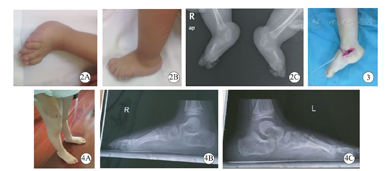

所有病例微创手术前均行手法+石膏固定,术前平均更换石膏6次(5~10次),手术时平均年龄16.5个月(5~35个月),随访时间平均43.2个月(12~63.6个月),最近随访平均年龄3岁6个月(1岁9个月至6岁3个月)。3例4足经过石膏矫形获得距舟关节复位,行经皮跟腱松解和经皮钢针固定复位的距舟关节;其余13例26足距舟关节未获得一期距舟关节复位但脱位程度明显改善,行小切口切开复位距舟关节直视下钢针固定和经皮跟腱松解;3例5足术中因僵硬程度大跖屈、内翻<20°,行胫前肌、伸踇长肌、伸趾肌及外侧腓骨长短肌延长;术后28足伤口均愈合良好,2足(6.7%)拆除石膏时伤口有渗出,经过换药后愈合。最近一次随访示30足有良好外观,典型病例见图2,图3,图4,足内侧纵弓出现;背屈活动:术前/术后10°(0°~20°)/22.5°(5°~35°)(P<0.001),跖屈活动术前/术后-10°(-20°~0°)/22.5°(5°~35°)(P<0.001),踝关节无明显功能障碍;足跟处于中和位5例9足,足跟外翻5°~8°的11例21足;2例3足(10%)术后1年随访发现有复发现象(跖屈活动<10°)站立位足跟有轻度外翻15°,摄片TAMBA35°,CAMBA10°,再次行石膏矫形4次后TAMBA10°,CAMBA5°,予以继续佩戴支具,同时白天穿垫足弓垫的矫形鞋。2例3足年龄大于4岁已终止矫形鞋只运用足弓垫。

术后1年足部X线片示平均TAMBA:术前71.3°(53°~98°)/术后4.3°(-5°~ 16°)(P<0.001),矫正65.8°(47°~85°);平均CAMBA:术前36.2°(14°~60°)/术后0.5°(-20°~ 10°)(P<0.001),矫正38.5°(21°-55°);平均跟距角:术前56.8°(40°~70°)/术后30.3°(20°~38°)(P<0.001),矫正25.8°(15°~45°)。13例26足(86.7%)术后效果为优(TAMBA-13°~9°);2例3足(10%)为良好(TAMBA分别是16°、13°和11°),1例1足可(3.3%)X线片显示有轻度距骨缺血性坏死,但行走无疼痛。